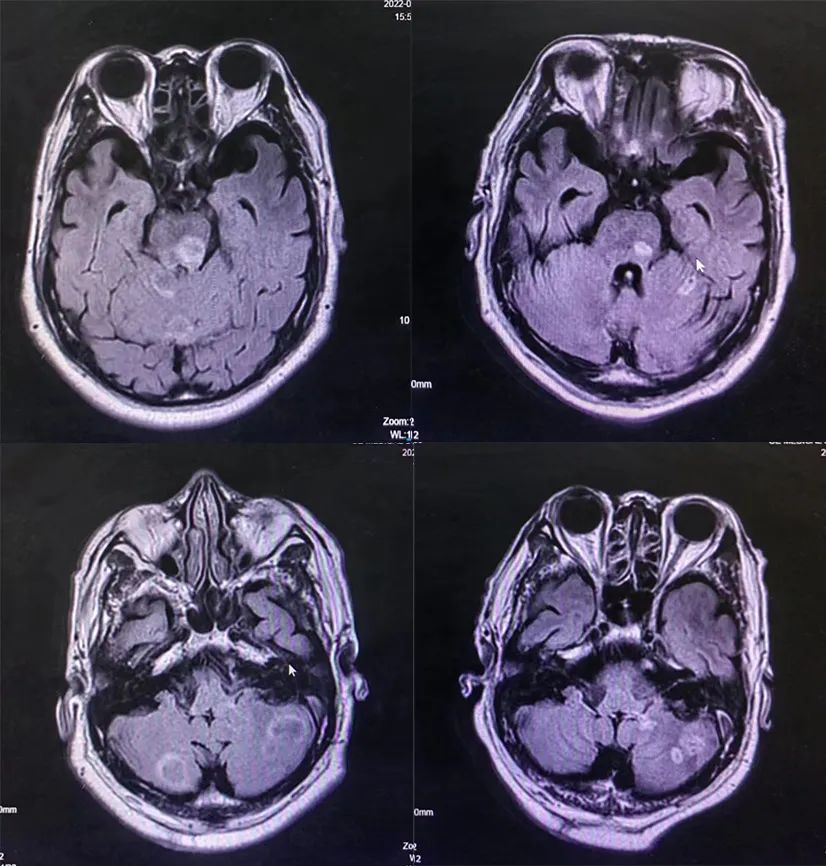

2022-07-04(免疫联合化疗3周期后)胸部CT:右肺下叶见毛刺样结节影,大小约11×13mm,右侧腋窝、左锁骨上窝、纵隔内见多发肿大淋巴结,部分较前减少。

2022-10-31(免疫单药维持治疗3周期后)胸部CT:右肺下叶毛刺样结节影,较前相仿,右侧腋窝、左锁骨上窝、纵隔内见多发肿大淋巴结,较前相仿。

图5.三线治疗后胸部CT

三线治疗疗效评估:颅脑PR、原发灶SD